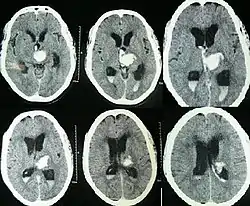

يعتمد التشخيص على التاريخ المرضي والفحص السريري، ومعرفة الحالة المصاحبة، بالإضافة إلى بعض الفحوصات الإشعاعية مثل :

- الأشعة المقطعية : وتعطي صور واضحة عن الحالة ومكان الانسداد.